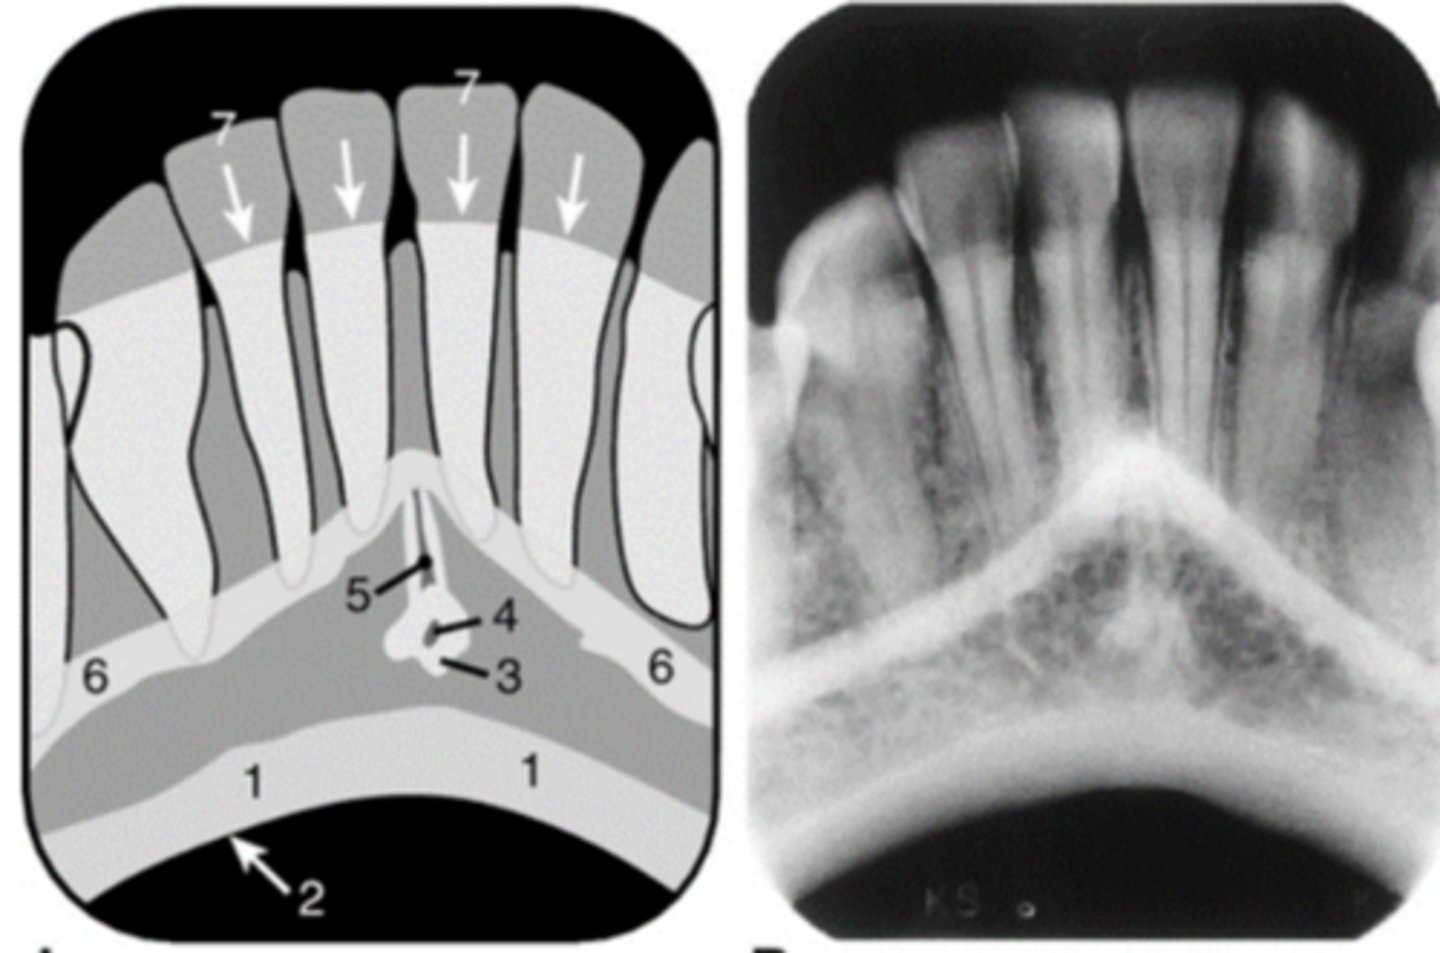

Nasopalatine (incisive) foramen

Identify the round, ovoid radiolucent structure indicated by the black arrows.

<p>Identify the round, ovoid radiolucent structure indicated by the black arrows.</p>

Nasopalatine canal

Identify the straight, radiopaque lines indicated by the white arrows.

<p>Identify the straight, radiopaque lines indicated by the white arrows.</p>

Nasal cavity

In which radiolucent space does the #6 lie?

<p>In which radiolucent space does the #6 lie?</p>

Lingual foramen

Name the small, radiolucent dot indicated by #4.

<p>Name the small, radiolucent dot indicated by #4.</p>

Superior foramina of the nasopalatine duct

Name the two round radiolucencies indicated.

<p>Name the two round radiolucencies indicated.</p>

67

New cards

Nasopalatine duct

What is the wide, vertical structure indicated by the arrows?

<p>What is the wide, vertical structure indicated by the arrows?</p>

68

nasolacrimal duct

Name the structure the black arrow is pointing to.

<p>Name the structure the black arrow is pointing to.</p>